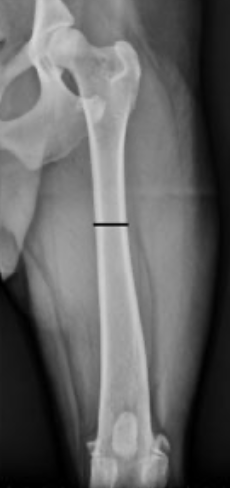

Identify the labeled structures

A

A = femur

B = patella

C = fibula

D = tibia